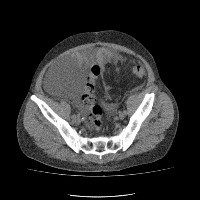

Regiao Renal

RegiaoRenal

regiao_renal